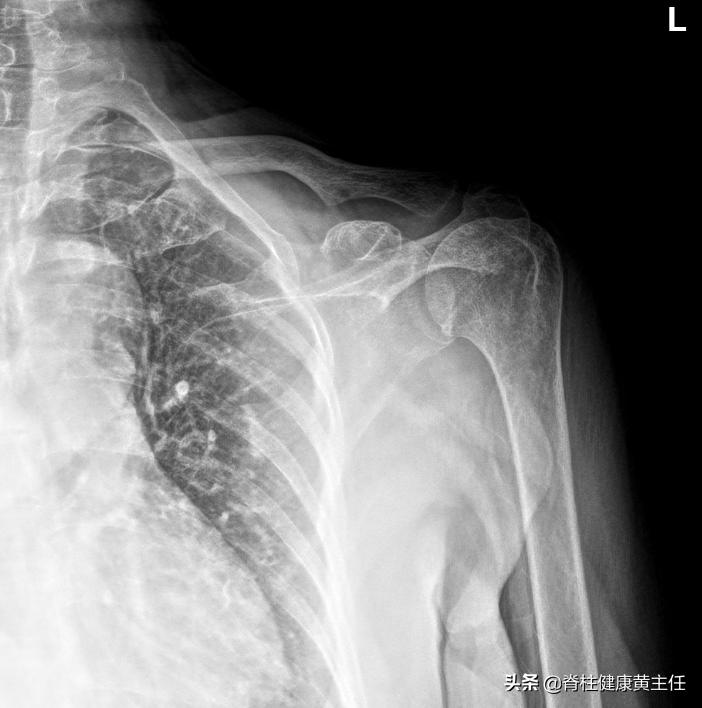

检查结果: 左侧肩关节诸构成骨质结构良好,骨皮质光滑、连续,骨小梁清晰,未见明显骨质破坏、增生、硬化等异常征;关节间隙如常,周围软组织层次显示清晰。